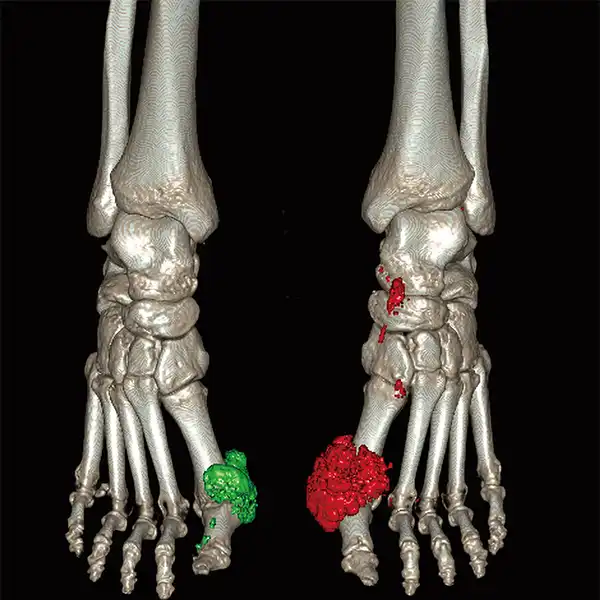

GENESIS Edition’s 16 cm wide area detector signicantly improves your ability to obtain high-quality images for routine and advanced studies. One rotation is all it takes to acquire a whole heart, a neonatal chest, a foot or an ankle exam – in a fraction of a second with less dose and great z-axis uniformity.

Adding dynamic functional imaging to morphology can provide valuable further insights, helping you to optimize disease management and treatment plans. Advanced perfusion maps can assist in diagnosis and therapy response verification of stroke or tumors, while dynamic joint studies help identify causes of pain or immobility.